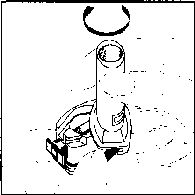

1. Kapağı çekip çıkarınız

2. Kapsül bölmesini açınız.

İnhalerin tabanını sıkıca tutup, açmak için ağızlığı üzerinde yer alan ok işareti yönünde döndürünüz.

3. Parmaklarınızın tamamen kuru olduğundan emin olunuz. Blisterden bir kapsül çıkarınız ve bu kapsülü cihazın tabanındaki kapsül bölmesine yatık olarak yerleştiriniz. Kapsülü, kullanmadan hemen önce blisterden çıkarmanız önemlidir.

ÖNEMLİ: Kapsülü ağızlığın İçerisinekoymayınız!

4. “Tık” sesini duyana kadar ağızlığı ok yönünün tersine döndürerek kapsül bölmesini kapatınız.

5. Tozu kapsülden serbestlemek için: